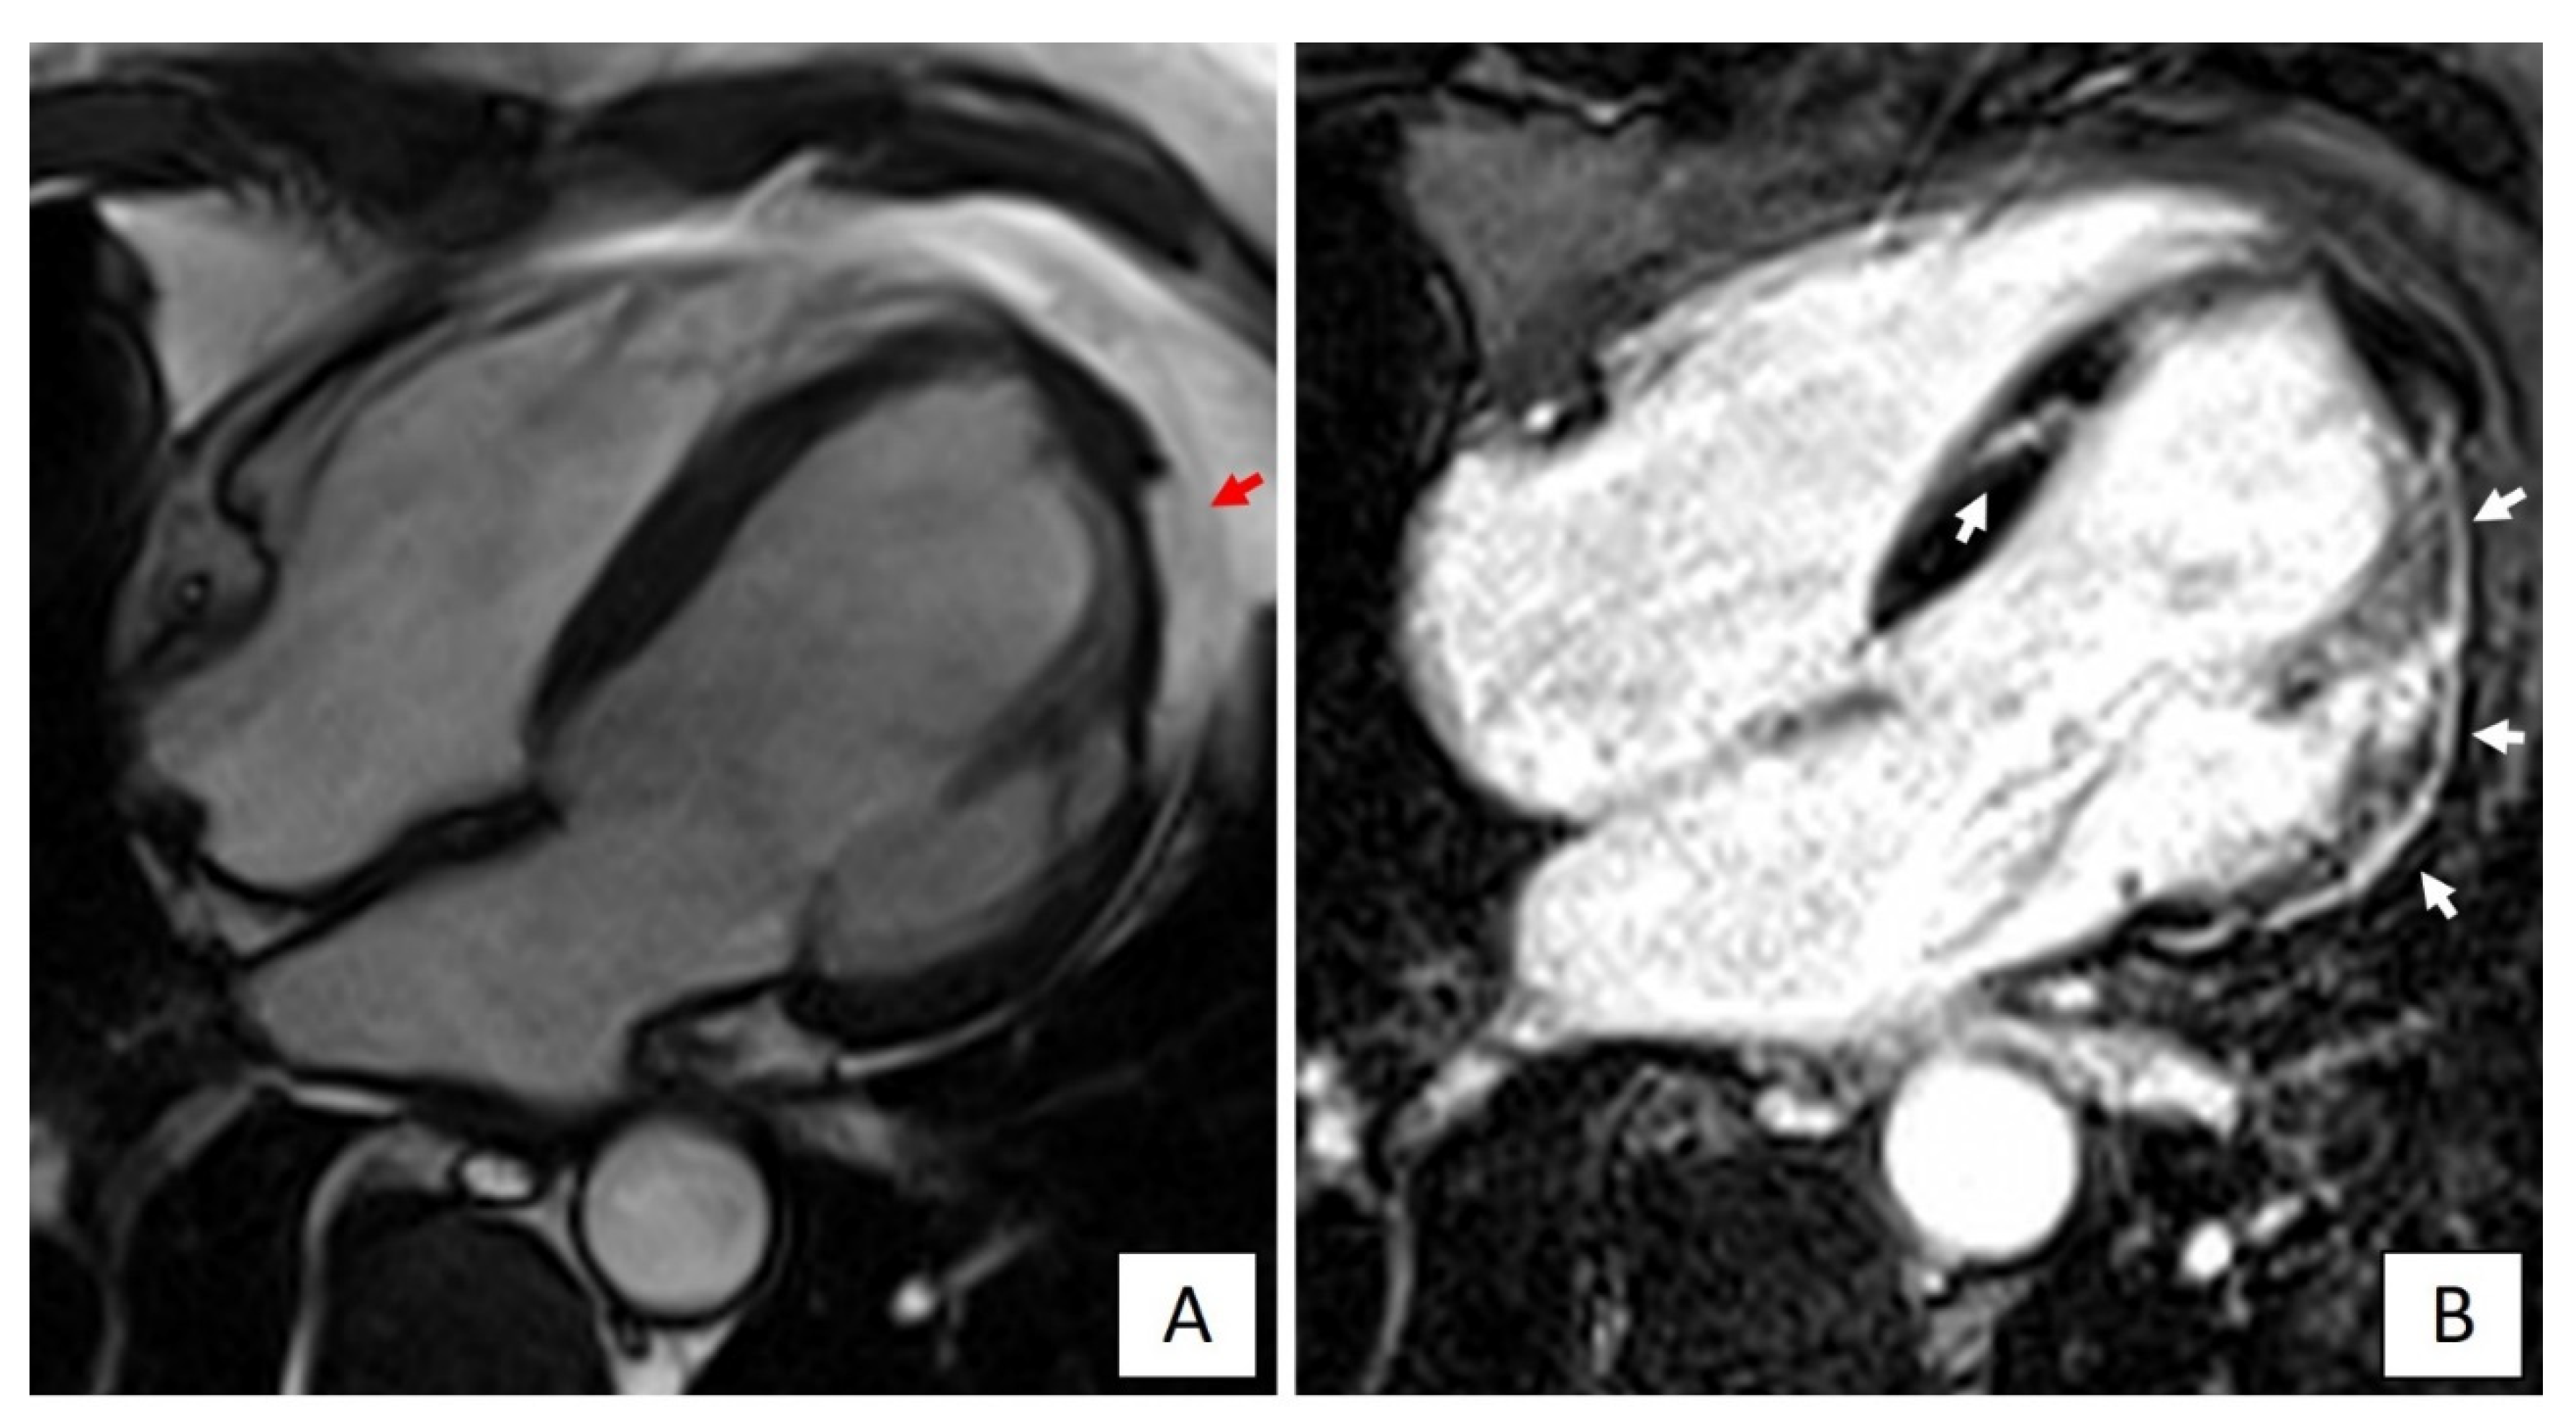

These characteristics substantiate the concept that the AC phenotype differs from that of DCM, being distinctively characterized by a large amount of LV myocardial fibrosis with prevalent subepicardial distribution, scarcely affecting the global LV systolic function, but acting as primary substrate for life-threatening VAs [63]. The recognition of the correct LV phenotype has significant implications for treatment, including indication for ICD that in AC patients may be considered even if the LV systolic function is not severely depressed [7]. With this regard, it must be emphasized that an imaging approach limited to a mere evaluation of the LV function, either global or regional, by echocardiography or cine-CMR appears insufficient to detect LV involvement. Conversely, LGE-CMR increases the diagnostic sensitivity because it allows identification of non-transmural LV scars. Since these scars commonly spare the subendocardial layers that mostly contribute to myocardial thickening, they may be undetectable by echocardiography (Figure 4) [63,64].

Figure 4.

Cardiac magnetic resonance imaging of a patient with DSP-related left dominant arrhythmogenic cardiomyopathy. (A) End-diastolic frame of cine cardiac magnetic resonance sequence in long-axis four-chamber view showing fatty infiltration of the lateral wall of the left ventricle (red arrow). (B) Post-contrast image showing myocardial fibrosis in the form of extensive late gadolinium enhancement in the lateral wall and septum of the left ventricle (white arrows).